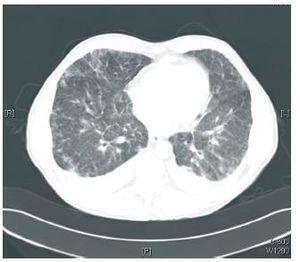

Los hallazgos de laboratorio mostraban 3.980 leucocitos/μl (eosinófilos 29,3%), hemoglobina 12,1 g/dl, plaquetas 276.000, creatinina 1,79 mg/dl, sodio plasmático 138 mEq/l, potasio plasmático 3,9 mE/l, y niveles plasmáticos de everolimus de 14 ng/ml. En la radiografía de tórax se observó un patrón intersticial bilateral, y en la TAC torácica, infiltrados y nódulos pulmonares con engrosamiento del intersticio bilateral (figura 1 y figura 2). La antigenemia y cultivo de citomegalovirus (CMV) fueron negativos, así como el antígeno de neumococo y Legionella. Se realizó broncoscopia con signos de broncopatía crónica, con resultados de BAL y BAS negativos. Se inició tratamiento empírico de amplio espectro antibiótico y antiviral, sin mejoria clínica y con empeoramiento radiológico, por lo que, con sospecha de neumonitis por everolimus, se decidió la retirada de este fármaco y la introducción de tacrolimus. El día posterior a la retirada de everolimus el paciente presenta mejorías clínica y radiológica progresivas con resolución del cuadro.

Figura 2. TAC torácica